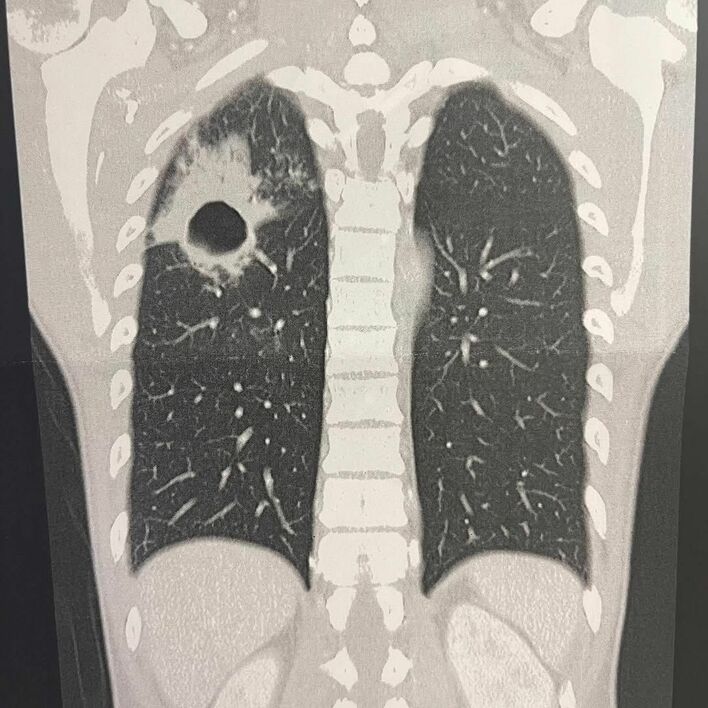

「撃たれとる!」アインシュタイン・河井ゆずる 肺の「衝撃写真」に驚きの声続々 “保湿ショット”も披露し肺膿瘍回復を報告

河井ゆずる 公式インスタグラムより